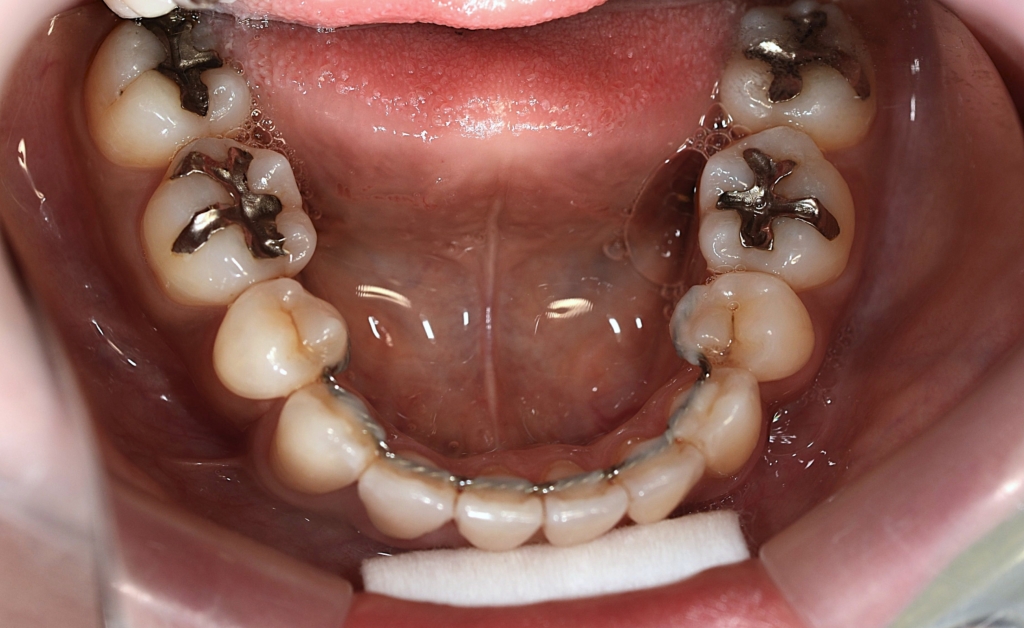

あらためて、矯正治療前後の歯並びと口元の変化を比べてみましょう。

まずは、歯並びの変化です。